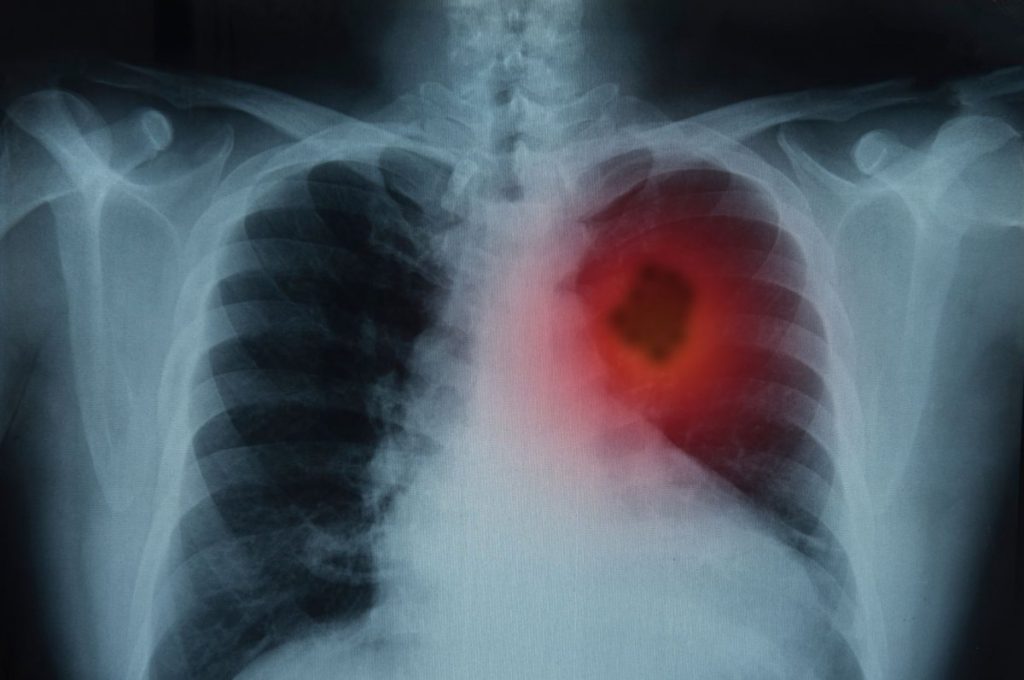

U maju 2017., LK je primio vest koja će mu zauvek promeniti život. Nakon epizode u kojoj je iskašljavao krv, 63-godišnji LK je otišao kod lekara. Vatrogasac 35 godina i pušač do pre 10 godina, LK je imao hronični proble sa kašljom tokom većeg dela svog života, pa je otišao kod lekara smatrajući da to nije ništa ozbiljno. Ali nažalost, bilo je ozbiljno – rečeno mu je da ima rak pluća stadijuma 1B u donjem levom režnju.

Kada je govorio o mogućnostima lečenja, njegov lekar mu je samo dao mogućnost operacije za uklanjanje tumora, ali to je LK bio neprihvatljiv. Nakon što je gledao majku kako se podvrgava operaciji za tumor na mozgu, znao je da želi da izbegne operaciju po svaku cenu. LK nije želeo da iskusi nuspojave koje mnogi pacijenti dožive posle operacije pluća, uključujući dugo vreme oporavka i probleme sa disanjem. LK je odlučio da preuzme stvari u svoje ruke i istražio mogućnosti lečenja raka pluća putem interneta, što ga je dovelo do neinvazivnog sistema CyberKnife®.

Septembra 2017. LK je otputovao na lečenje, koje je trajalo ukupno tri dana. LK je bio šokiran koliko je bezbolan i udoban tretman CyberKnife-om. Mogao je da ode u prodavnice, izađe da jede i vidi neke od znamenitosti grada tokom tretmana. Najbolje od svega, nakon tretmana kada se vratio u kući, LK je bio u stanju da nastavi sa svojim napornim danom, uključujući pomaganje supruzi da upravlja kozmetičkom salonom, bez neželjenih efekata. Prema njegovim rečima: „Bilo je lakše nego otići stomatologu.“ U stvari, njegov tretman CyberKnife-om bio je tako lak da LK je bio pomalo skeptičan ako deluje. Ali to je bilo tp – LK se vratio u martu 2018. na pregled i tumor je nestao – ostao je samo „vazdušni prostor“ kako ga nazivaju. Prošlo je više od 2 godine od tretmana LK Sajber nožem-a i on rado hvali da je pobedio ovu najtežu bolest i da je u dobrom zdravstvenom stanju. Raduje se sledećem zdravom pregledu i širenju svoje neverovatne priče o radiohirurgiji CyberKnife-om.